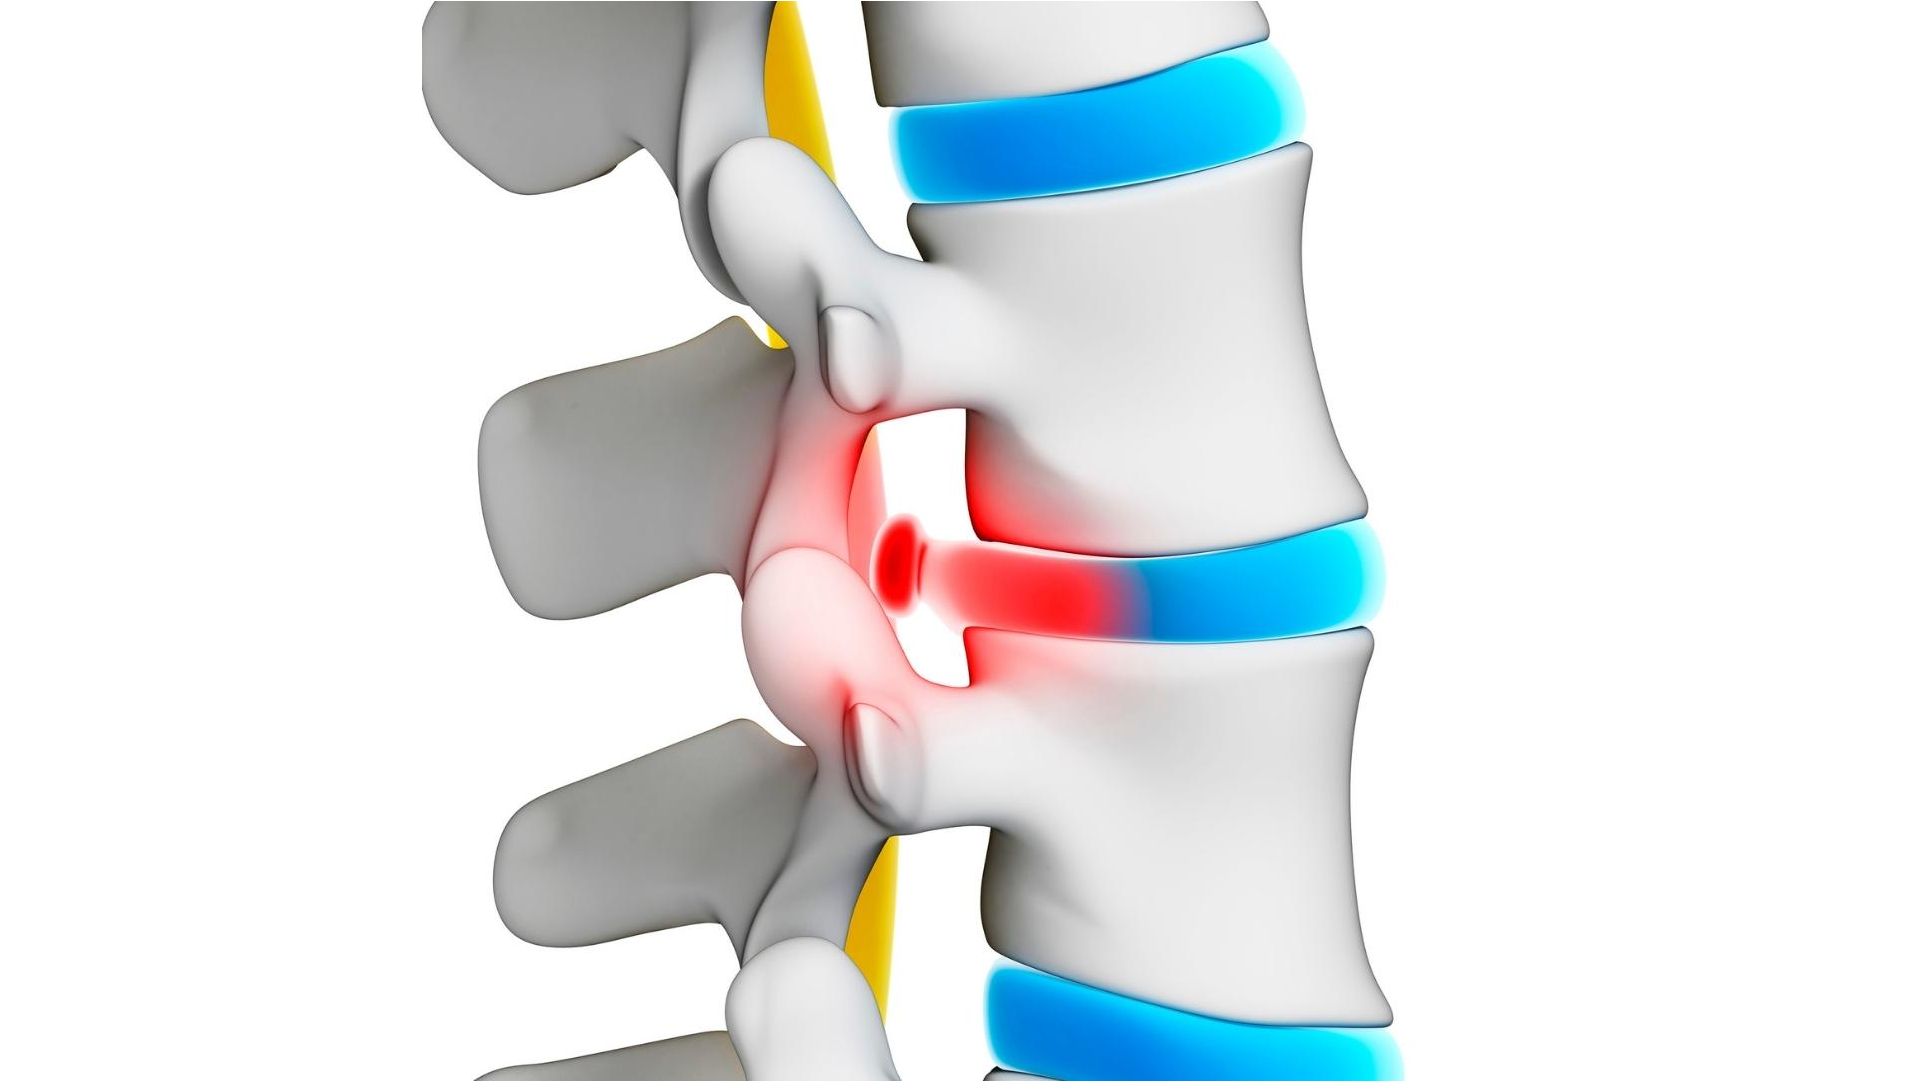

'This is a summary of what you will learn in this article: Understanding Lumbar Degenerative Disc Disease (DDD) - Lumbar DDD is a condition where spinal discs wear down, causing pain and stiffness. It's not a disease and doesn't always lead to disability. Lifestyle changes and understanding the condition can mitigate its impact on daily life. The Truth About Conventional Treatments - Surgery and medications are common treatments but come with risks, side effects, and long-term consequences. They are not the only options, and alternatives like physical therapy and lifestyle changes can be highly effective. A Comprehensive Guide to Natural Relief - Quick relief strategies, safe long-term solutions, and a step-by-step guide to healing a herniated disc are provided. Techniques include targeted exercises, dietary changes, stress management, and more, all focusing on natural, non-invasive methods. Debunking Common Myths - Separating fact from fiction reveals that Lumbar DDD is manageable without extreme measures. Natural healing is not a hoax but a valid and often preferable path, supported by scientific research and real-life success stories.'